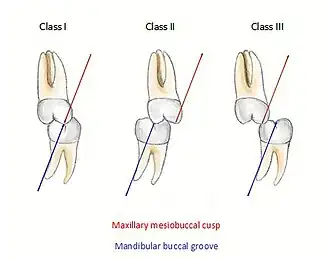

When discussing the occlusion of the posterior teeth, the classification refers to the first molars and may be divided into three categories:

- Class I: The mandibular first molar occludes mesially to the maxillary first molar, with the mesiobuccal cusp of maxillary first molar occluding in the buccal groove of mandibular first molar

- Class II: The mesiobuccal cusp of the maxillary first molar occludes anterior to the buccal groove of the mandibular first molar

- Class III: If the mesiobuccal cusp of the maxillary first molar occludes posterior to the buccal groove of the mandibular first molar[8]

Any deviation from the normal relation of teeth (Class I) is considered a malocclusion.

Class I relationships are thought to be “ideal”, however this classification does not take into consideration the positions of the two TMJ’s. Class II and III molar and incisor relationships are thought to be forms of malocclusion, however not all of these are severe enough to require orthodontic treatment. The Index of Orthodontic Treatment Need is a system that attempts to rank malocclusions in terms of significance of various occlusal traits and perceived aesthetic impairment.[11] The index identifies those who would benefit most from orthodontic treatment and onward referral to an orthodontist.